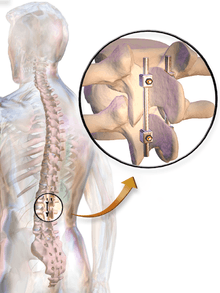

Posterolateral fusion places the bone graft between the transverse processes in the back of the spine. These vertebrae are then fixed in place with screws and/or wire through the pedicles of each vertebra attaching to a metal rod on each side of the vertebrae.

In most cases, the fusion is augmented by a process called fixation, involving the placement of metallic screws (pedicle screws often made from titanium), rods, plates, or cages to stabilize the vertebrae and facilitate bone fusion. The fusion process typically takes 6 to 12 months after surgery. During this time external bracing (orthotics) may be required. External factors such as smoking, osteoporosis, certain medications, and heavy activity can prolong or even prevent the fusion process. If fusion does not occur, patients may require reoperation.

In spinal fusion, the accuracy of screw insertion into the pedicles directly affects surgical outcome. Accurate placement generally involves considerable judgmental skills developed through lengthy training. Because the impact of misaligning one or more pedicle screws can directly affect patient safety, a number of navigational and trajectory verification approaches have been described and evaluated in the literature to provide some degree of guidance to surgeons. For example, Manbachi et. al (2013) presented an overview of the need and the current status of the guidance methods available for improving the surgical outcomes in spinal fusion. They also describe educational aids that have the potential for reducing the training process.[6] Accurate guidance systems, such as the Mazor Robotics "Renaissance", have been developed to assist with spinal fusion procedures.